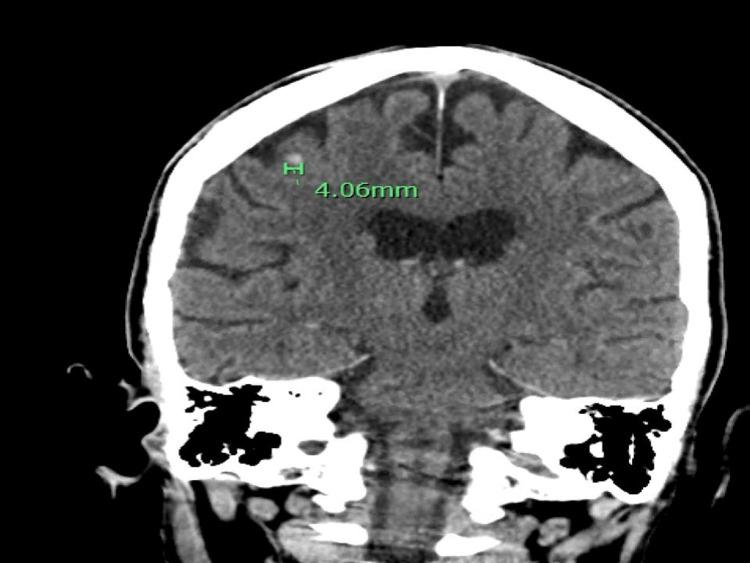

Sarcoidosis is a systemic granulomatous disease characterized by the hyperactivation of CD4 T cells, CD8 T cells, and macrophages. Clinical presentations of sarcoidosis are highly variable. Sarcoidosis is unknown in its etiology, but it suggests it may result from exposure to specific environmental agents in genetically susceptible people. Sarcoidosis commonly involves the lungs and lymphoid system. Bone marrow involvement in sarcoidosis is uncommon. Sarcoidosis rarely results in intracerebral hemorrhage due to severe thrombocytopenia secondary to bone marrow involvement. We present the case of a 72-year-old woman who has been in remission from sarcoidosis for 15 years and developed intracerebral hemorrhage secondary to severe thrombocytopenia due to sarcoidosis recurrence in the bone marrow. The patient presented to the emergency department with a generalized, non-blanching petechiae rash and nose and gum bleeding. Her labs showed a platelet count of less than 10.000/mcL, and computed tomography (CT) showed intracerebral hemorrhage. A bone marrow biopsy revealed a small, non-caseating granuloma indicative of a sarcoidosis relapse in the bone marrow.

结节病是一种全身性肉芽肿性疾病,其特征为CD4 T细胞、CD8 T细胞和巨噬细胞的过度活化。结节病的临床表现高度多变。结节病的病因尚不清楚,但提示可能是在基因易感人群中接触特定环境因素所致。结节病通常累及肺部和淋巴系统。结节病累及骨髓并不常见。由于骨髓受累继发严重血小板减少,结节病很少导致脑出血。我们报告一例72岁女性病例,该患者结节病已缓解15年,因骨髓结节病复发继发严重血小板减少而发生脑出血。患者因全身性非压之褪色的瘀点皮疹以及鼻出血和牙龈出血就诊于急诊科。她的实验室检查显示血小板计数低于10,000/微升,计算机断层扫描(CT)显示脑出血。骨髓活检显示一个小的非干酪样肉芽肿,提示骨髓结节病复发。